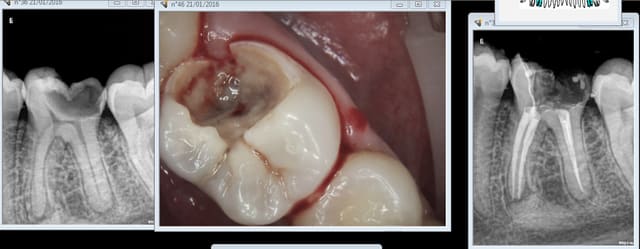

Pour moi l'image de marque du cabinet ne se voit pas. Par contre ca me gênerait de faire une provisoire sur une endo pourrie comme j'en vois souvent -)))

Capture d e cran 2016 01 21 16.30 - Eugenol

Tiens mon cher Bjorn , amuse toi , elle date de ce matin tout frais moulu . Mince, prends une loupe, ça dépasse ? manque un canal ? pas la digue ? rhaaaa je vais en enfer ou j'ai encore le droit de poster ?

Chicot faut m'excuser j'ai pas les photos !

Il y en a qui en mettent trop de la gutta et d'autres pas. Ca fait une moyenne. -))

tiens ? mais je vois qu'on fait aussi des inlay core ! -)

Capture d e cran 2016 01 21 17.43 - Eugenol